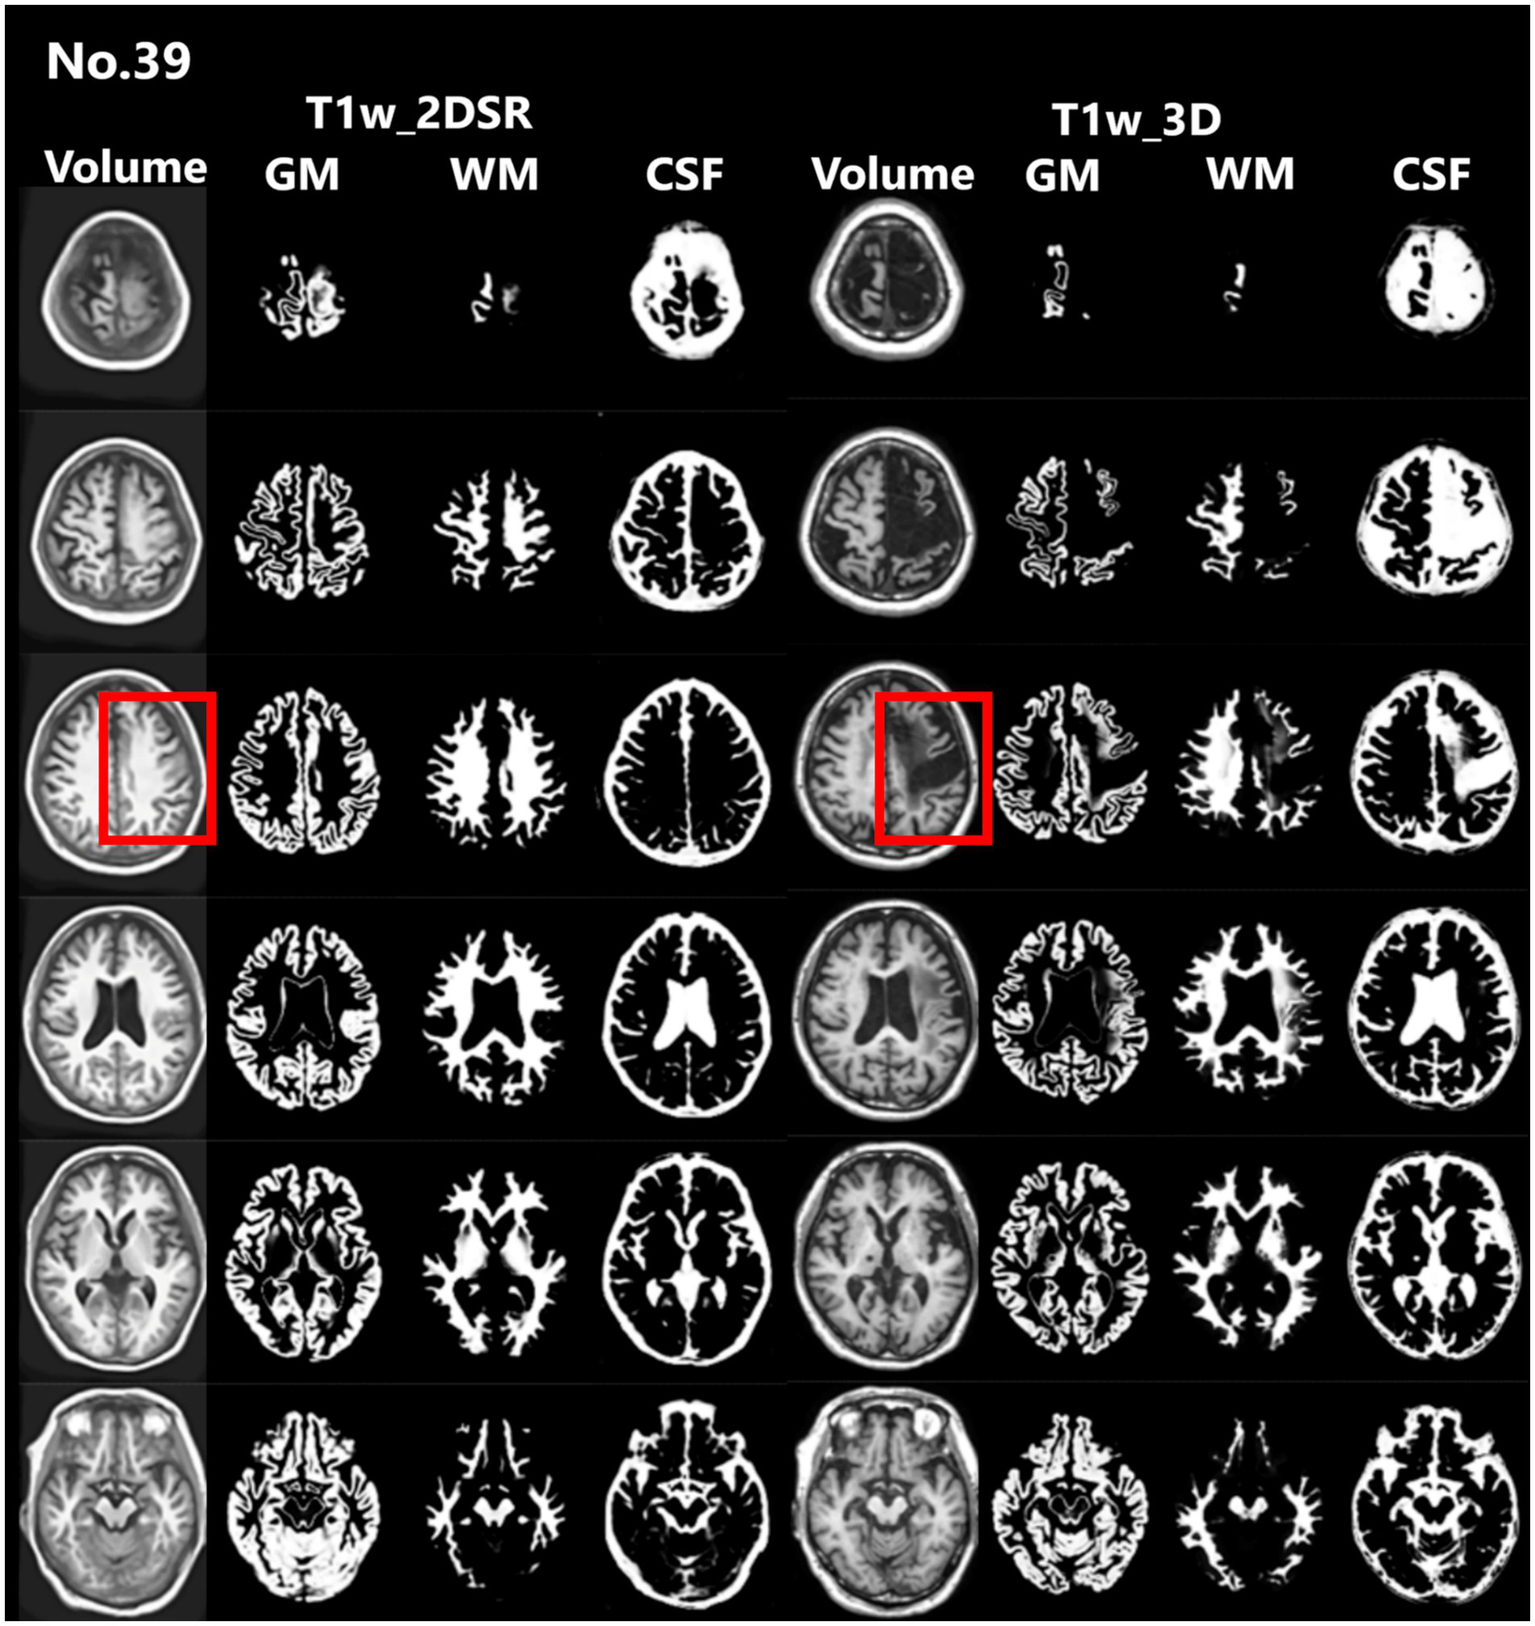

Several versions of VSRAD have been developed. In this study, we used “VSRAD advance,” which was based on SPM 8 and incorporated DARTEL (11, 22, 23). VBM was performed on both T1w_2DSR and T1w_3D, yielding data on segmented white matter (WM), gray matter (GM), CSF (Figure 2). Four Z-scores reflecting the degree of atrophy in the specific volume of interest (VOI) were automatically calculated and provided by VSRAD advance, based on comparing each patient’s data with an internal database of 80 healthy volunteers. The Z-score was defined as [(control mean) – (individual value)]/(control standard deviation) (11). The Z-scores generated by VSRAD advance visualize and quantitatively evaluate the degree of gray matter atrophy in the regions of interest, primarily the parahippocampal gyrus including the medial temporal lobe, which is closely associated with Alzheimer’s disease, by measuring the degree of deviation from the normative brain database. The four scores were as follows: Score 1 “Severity”: Z-score reflecting the severity of GM atrophy in the VOI. Score 2 “Extent”: the extent of GM atrophy in the VOI. Score 3 “Ratio”: the ratio of the extent of GM atrophy in the VOI to the whole brain. Score 4 “Maximum”: the maximum z-score of the severity of GM atrophy in the VOI of AD (24–28). To mitigate volumetric inaccuracies introduced by non-linear spatial normalization and Gaussian smoothing in the DARTEL pipeline, intermediate WM and GM segmentation files were used for estimating native-space volumes. Total brain volume was calculated as the sum of the WM and GM volumes (WM + GM). Measurements were performed using the Segment Statistics module of 3D Slicer (13).

Figure 2. Segmented images obtained by VSRAD. The left panel shows the VSRAD analysis results using the SynthSR-based method (T1w_2DSR). Segmented gray matter (GM), white matter (WM), cerebrospinal fluid (CSF) images were successfully generated. The right panel shows the comparison of segmented GM, WM and CSF images using the standard method (T1w_3D). These results indicate that the volume data generated by SynthSR demonstrated comparable segmentation performance to 3D data from standard methods.

Seventy-five patients underwent MRI during the study period. Of these, 21 (28.0%) were male. The mean age was 83.5 years (range, 61–107 years). This cohort reflects the typical population undergoing dementia screening in Japan. For all cases, 3D volume data (T1w_2DSR) were successfully generated from T1w_2D using SynthSR. The generated T1w_2DSR did not reconstruct the parietal CSF region because it was not imaged in the original T1w_2D. Each output image was independently reviewed by two neurosurgeons. Cases with obvious motion artifacts and disrupted WM and GM segmentation in the control T1w_3D images were excluded from the analysis. Among the excluded cases, four (Cases 22, 26, 43 and 63) had showed segmentation errors involving the ventricles and GM due to brain atrophy (Figure 3), five (Cases 7, 11, 12, 69 and 72) showed segmentation failure caused by motion artifacts; and two (Cases 15 and 39) had structural brain lesions due to stroke (Figure 4). A total of 64 cases were analyzed after excluding 11 cases. After VSRAD analysis, four scores and three volumes were calculated. For these evaluated indices, normality was not met in most cases (Shapiro–Wilk test, p < 0.05), and thus non-parametric comparisons were adopted.

Figure 4. Representative excluded cases of stroke. Case no. 39 shows a patient with structural brain lesions due to stroke. In the 3D volume data acquired using the standard method, a low-signal area was observed in the left frontal lobe, consistent with cerebral infarction. In contrast, in the 3D volume generated by SynthSR, the lesion area appeared artificially filled in (red rectangles).